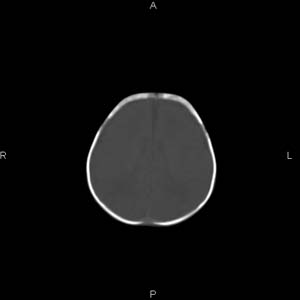

患者男,27天,出生后正常,今天中午在母亲怀里抱着吃奶在放下睡觉时发现后枕部慢慢出现一包块,来查头颅ct。无外伤史。包块内ct值47-51hu。请大家讨论。

头皮下血肿,局部枕骨略有凹陷

枕部皮下血肿 局部枕骨凹陷

颅骨无缺损,骨缝无增宽.支持头皮血肿(血管破裂)